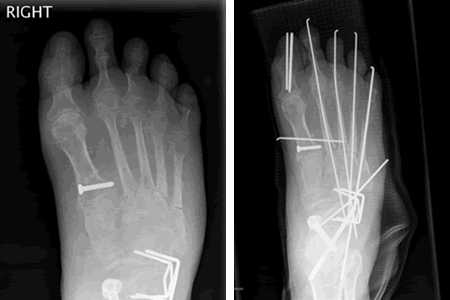

At 28 and already having sixteen surgical procedures behind me, life was not going as I had planned. I had left three jobs in the last year, one which I really loved, all because of the severe foot pain that I lived with everyday. The cause of the pain made a solution especially difficult. I had a congenital neuropathy called, Charcot Marie Tooth Disease, and a bone disease known as, Osteogenesis Imperfecta, along with many serious injuries over the past ten years making mine an especially complicated case. My body felt much older than it's young looks betrayed.

I was referred to Doctor Leavitt at the very beginning of 2008. When I met Dr. Leavitt for the first time I left knowing two things. First, my case would be difficult and even impossible for most surgeons (in fact many doctor's in the past refused to operate on me because of the complicated nature of my case). Second, Dr. Leavitt was the right man. I've never left a consultation feeling both so overwhelmed at what was in store for me in terms of pain, recovery, and rehab and yet so at ease that I was in the most capable hands. To say Dr. Leavitt is thorough would be an understatement. In fact, I had four visits in the month leading up to my surgery and I even received a phone call on a Sunday afternoon from Dr. Leavitt to confirm something he was working on at home. I took comfort knowing that I was going into a situation that had been planned out down to every detail and every contingency was accounted for. Simply put, Doctor Leavitt is the most accessible and capable doctor I have ever met.